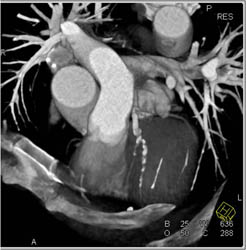

Diseased RCA With Patent Stent